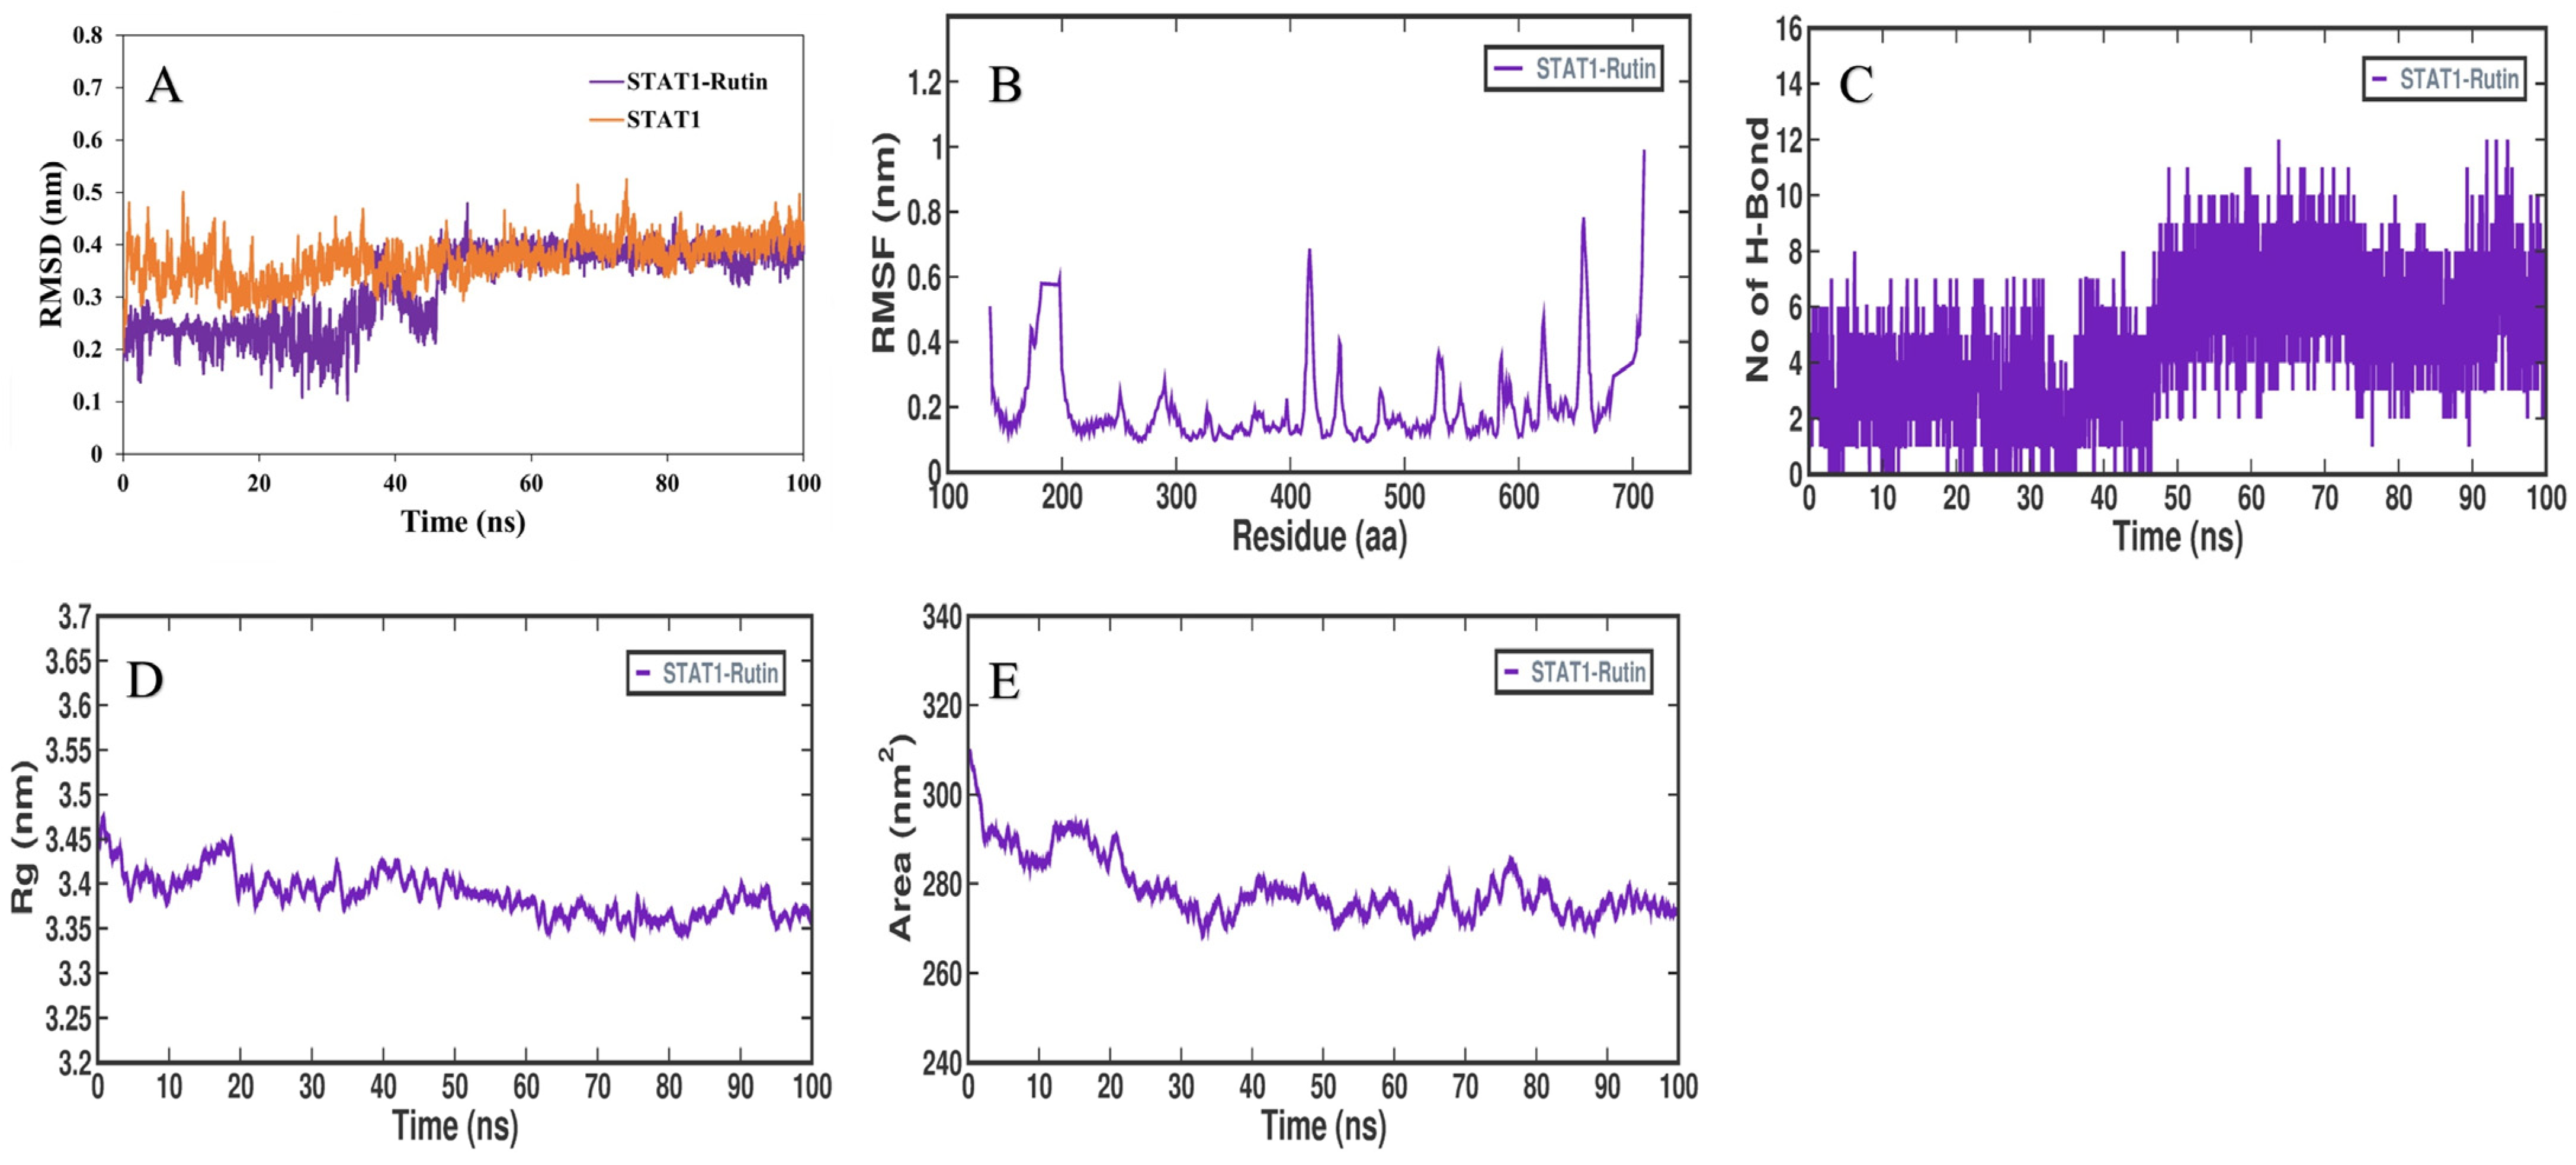

3.5. MD Simulation Analysis

3.6. MMPBSA Binding Free Energy